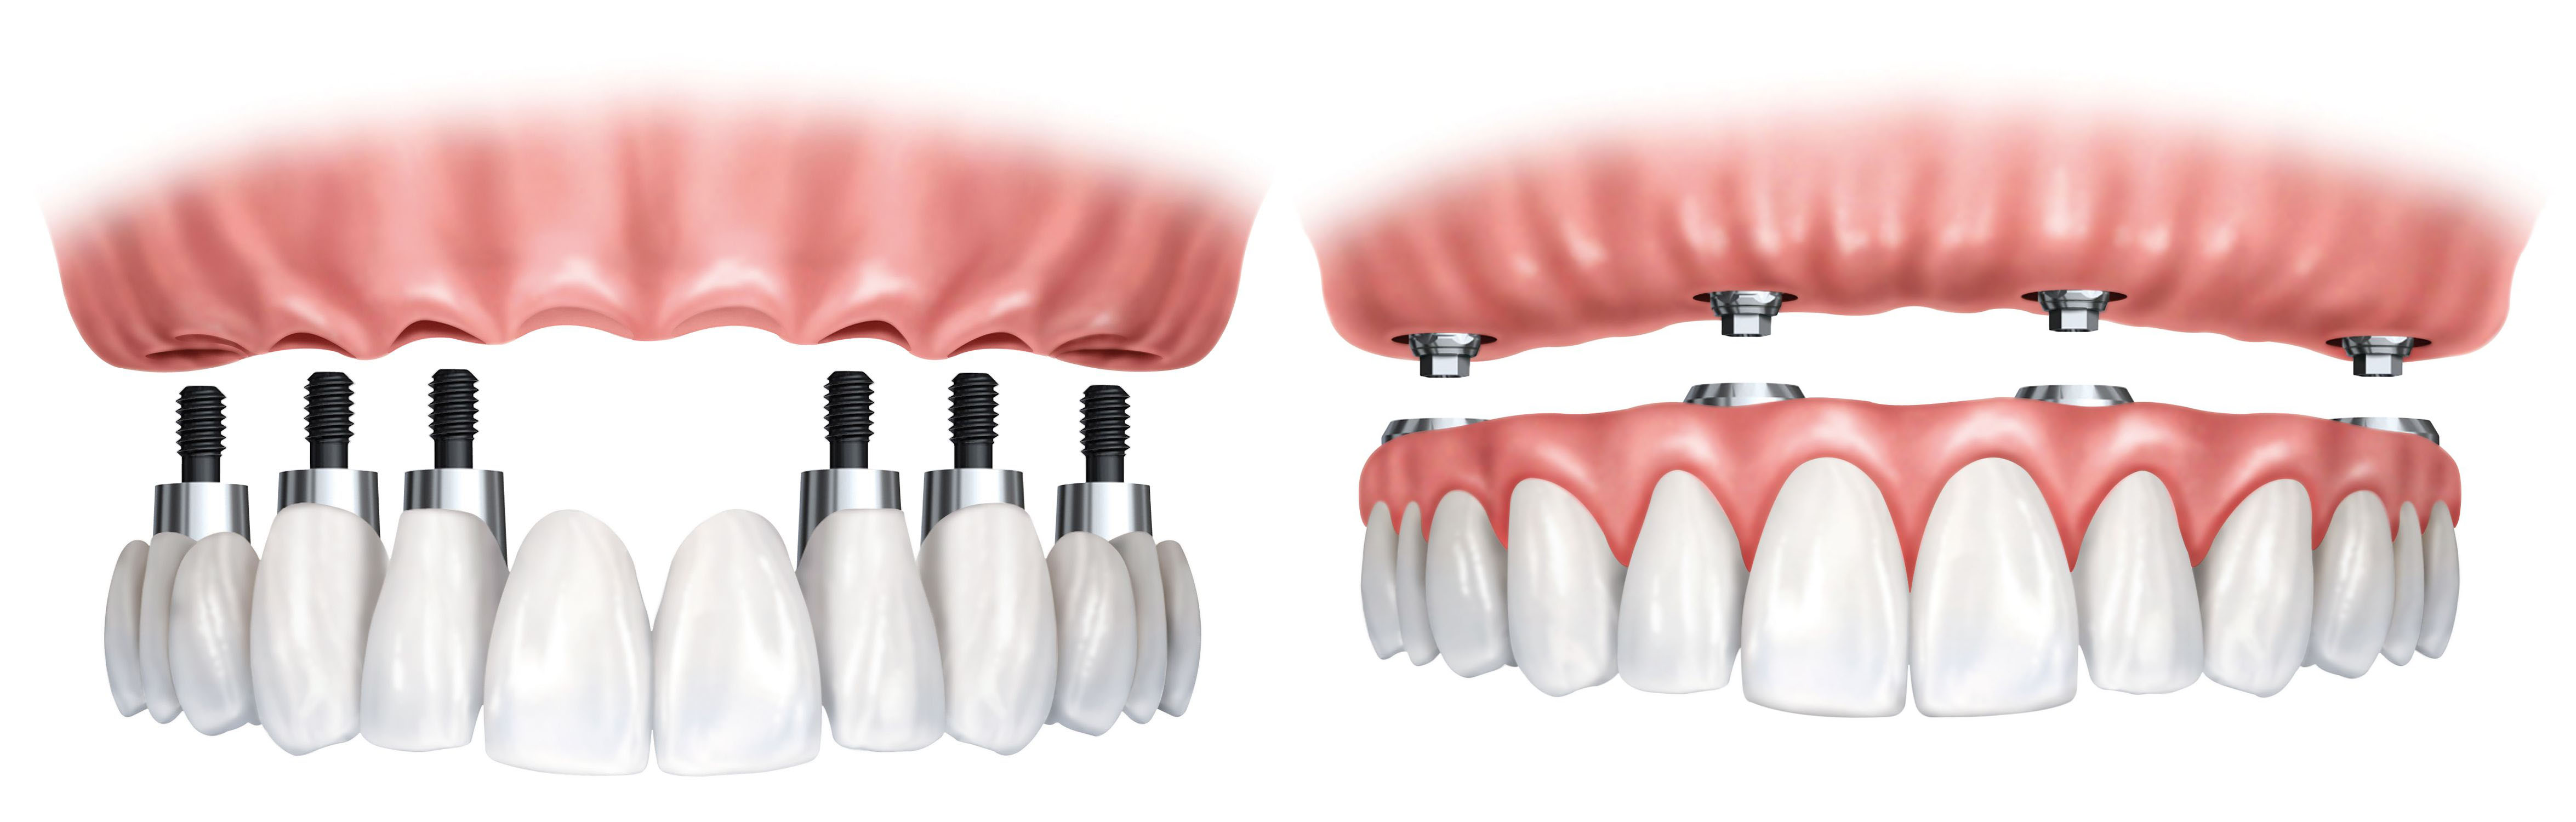

REMOVABLE IMPLANT SUPPORTED DENTURES

Removable implant-supported dentures also known as snap-on dentures are godsend options to patients who desire an economical solution to loose dentures. In this particular procedure, the denture for the upper jaw is connected to a ball or a bar attachment, which in turn is anchored on two or more mini dental implants in the front part of the upper jaw. Even though this can be done and is more economical, the success rate of fixed teeth in 3 days is much higher and therefore more recommendable.